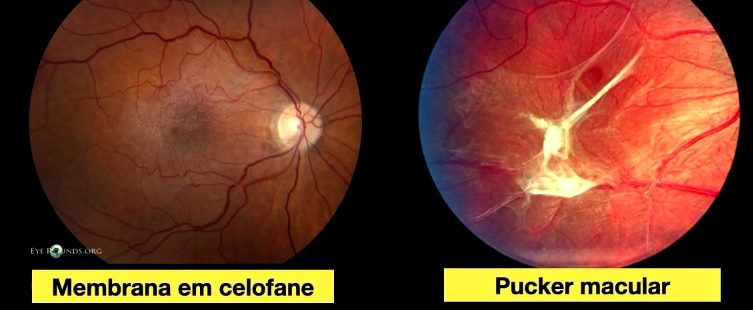

MER em celofane (quadro leve)

- 66% com AV > 20/30

- 5% com AV<20/30

Pucker Macular (quadro avançado)

- pós-cirúrgico –> distorção vascular

- BAV importante